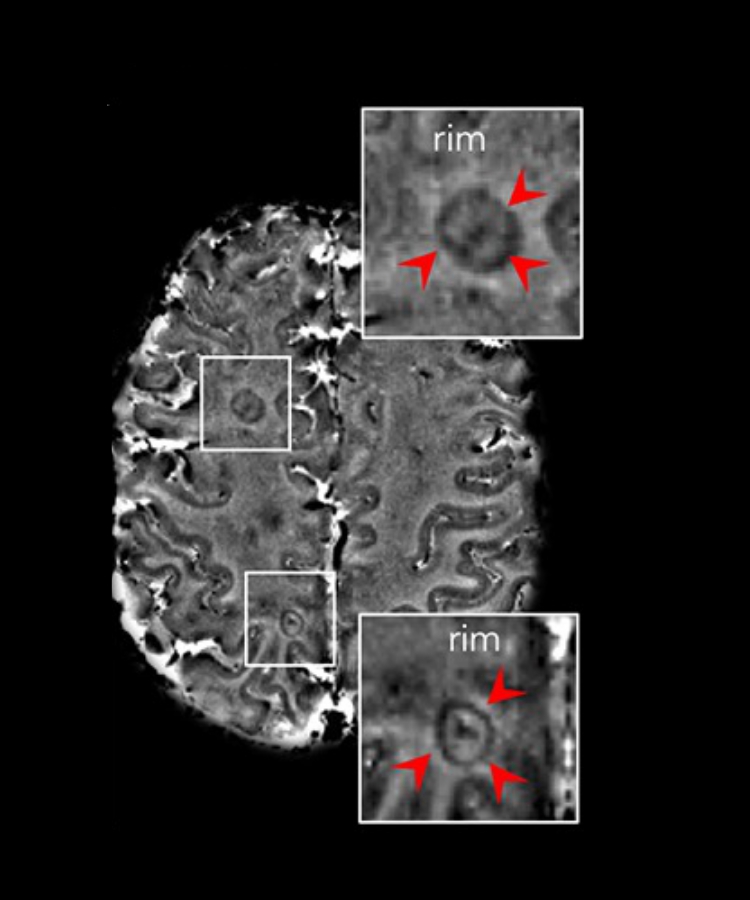

MiST-MS includes two major lines of research. The first aims to understand which molecular mechanisms are responsible for premature brain aging linked to chronic inflammation in multiple sclerosis patients. Patient blood or skin cells will be used, which, through specific in vitro treatments, will be reverted to the stem cell stage and subsequently differentiated into microglial cells, the main immune cells within the central nervous system, involved in inflammation. Thanks to this advanced technique, it will be possible to study directly on these cells, using genome editing and next-generation sequencing approaches, what cellular and genetic mechanisms are involved in the process of brain cell senescence. The second line of research, more clinically oriented, stems from an important observation recently made by Martina Absinta’s team. In people with multiple sclerosis, different types of lesions may appear in the central nervous system, with characteristics and consequences that vary depending on the type. Patients with chronic active lesions show reduced tissue repair capacity and less favorable disease progression. These lesions, identified by MRI, appear as “rings” with dark rims.

The goal is to understand how these lesions determine a worse prognosis, by assessing differences in glial and neuronal cell behavior in patients with many chronic lesions compared to patients without them.

Initially, there were no ways to distinguish chronic active lesions from others through MRI, meaning that there was no way to identify early the patients at higher risk of clinical deterioration and disability.

“In 2012 I was working at the National Institutes of Health in the United States, using high-field magnetic resonance imaging (7 tesla), which allowed to achieve exceptional levels of detail. Already from the first patient’s scans, I noticed that some lesions had a dark rim, and others did not. I thought that if those with this feature matched the chronic active lesions that at the time we could only see in autopsies, then we had a marker to distinguish these patients early—and that’s exactly what happened,” explains Martina Absinta. “I devoted the next decade of my research to this aspect, which is now well studied by many other neurologists and researchers, to the point it has reached international consensus. This marker has been also recently included in the diagnostic criteria for multiple sclerosis.” The hope is to increasingly personalize therapies, making them more effective.